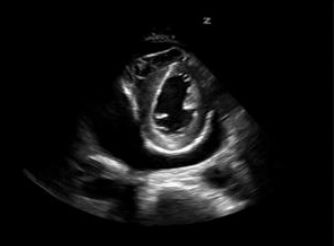

26. 60 歲男性,有肺癌病史,因胸悶及呼吸窘迫被送至急診,血壓 85/50mmHg, 脈搏 116 下/min,呼吸 28 次/min,體溫 36.5°C,心臟超音波胸骨旁短軸介面(parasternal short axis view)影像如下圖,請問最有可能為何種診斷? (A)氣胸。 (B)肺動脈栓塞。 (C)縱膈腔氣腫。 (D)心包膜積水。 (E)心內膜炎。